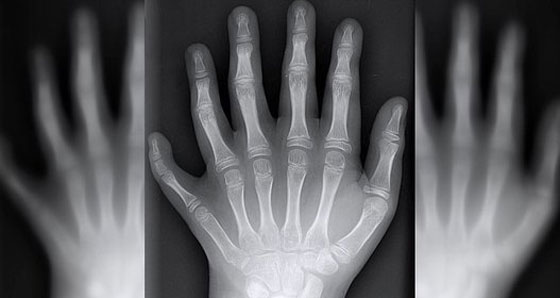

وتسمى المتلازمة الوراثية التي تتسبَّب في أن يُولَد الناس بأصابع أيدي وأقدام إضافية بـ"كثرة الأصابع Polydactyly" وهي متلازمة شائعة نسبياً، إذ تحدث مرة بين كل 3000 حالة ولادة، غير أنَّ تلك الطفرة أكثر شيوعاً في بعض أنحاء العالم من غيرها. لكن، في حين أن معظم من يُولَدوا بأصابع أيدٍ أو أقدامٍ إضافية يعجزون عن استخدامها، تُعتَبَر عائلة دا سيلفا غير اعتيادية؛ إذ يتمكَّنون من استخدام كل أصابعهم بشكل طبيعي.